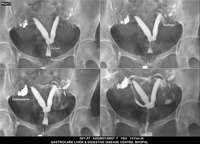

Section: HSG

Total: 49 Cases